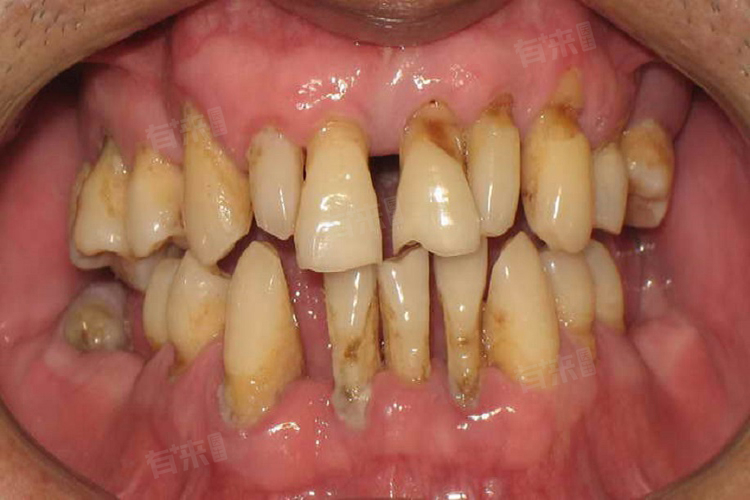

长期不及时治疗牙周炎,会导致炎症向周围牙周组织蔓延,影响到牙齿的固定,患者会发现牙齿逐渐变得松动,甚至脱落。

长期的炎症反应导致牙龈组织的破坏和萎缩,牙龈边缘逐渐向根方退缩,暴露出牙齿根部,使牙齿显得更长。